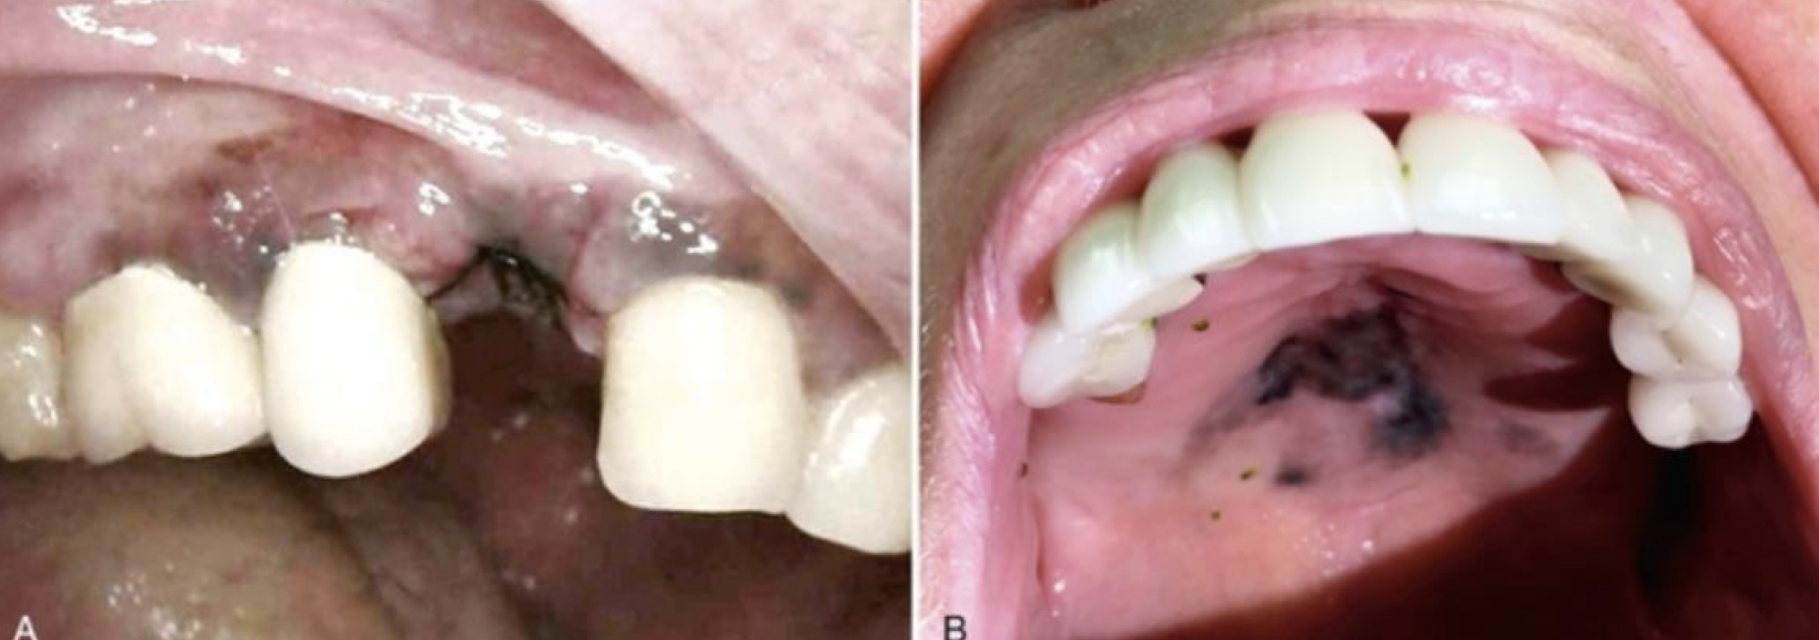

heterogenous oral melanoma

oral melanoma

describe site distribution in primary head and neck mucosal melanoma

nasal cavity (47.5%), hard palate and gingiva (15%), alveolus (11.5%), sinonasal cavity (10%)

what is the management for oral melanoma management?

Primary rx – excision with clear margins or radiation

50% recurrence

Nodal and distant mets in upto 65%

5 year survival is 10-20% (from mets)

oral pigmented lesions are considered ?

melanoma until proven otherwise

high risk sites of oral pigmented lesions include

maxillary gingiva and hard palate